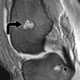

Multiple enchondromas

An enchondroma is a benign cartilage tumour found inside bones. Typically, enchondroma is discovered on an X-ray scan. [Source: Wikipedia ]